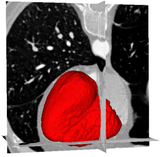

Ventricles Segmentation for Diagnosis of Cardiac DiseasesThis work presents an automatic method for extracting the myocardial wall of the left and right ventricles from cardiac CT images. In the method, the left and right ven- tricles are located sequentially, in which each ventricle is detected by first identifying the endocardial surface and then segmenting the epicardial surface. More... New: L. Zhu, Y. Gao, V. Appia, A. Yezzi, C. Arepalli, T. Faber, A. Stillman, A. Tannenbaum. A Complete System for Automatic Segmentation of Left Ventricular Myocardium from CT Images using Shape Decomposition and Contour Evolution, IEEE Transaction on Image Processing(TIP), in submission. |